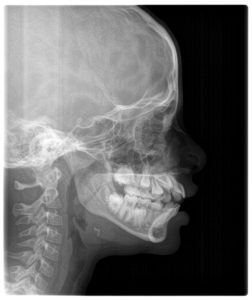

Through clinical tests and radiographs, we explored whether Amaira’s mouth breathing was due to physical blockage or an acquired habit.

Key Findings

- Narrow upper jaw (palate)

- Open bite with dental spacing

- Lip incompetence at rest

- Habitual mouth breathing pattern

- Enlarged adenoids without full obstruction